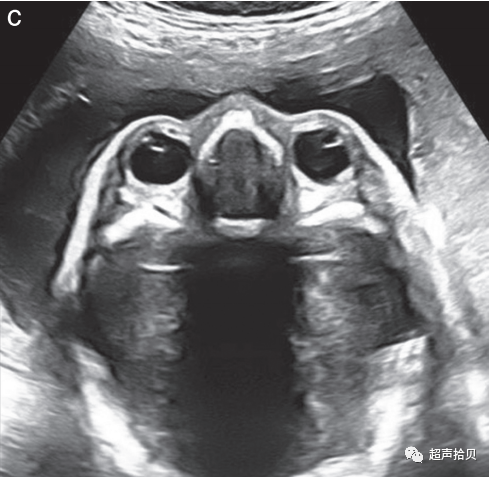

1. 胎儿颜面部的评估应包括冠状面(正面)显示上唇,以评价有无唇裂畸形唇裂(图3a);

2. 如果技术上可行,还包括正中矢状面(图3b);

3. 应该检查眼眶的存在和正常的位置以及眼睛的距离(图3c);

图3胎儿颜面部的超声图。

(a)口腔、嘴唇和鼻子通常通过冠状面进行评估。

(b)如果技术上可行,应获得面部中矢状面,因为它为双侧唇裂、前额凸起、小颌畸形和鼻骨异常提供了重要的诊断线索。(请注意,鼻骨检查是可选的)

(c)两个胎儿眼眶应呈现对称和完整,眼睛间距约为一个眼眶的直径。